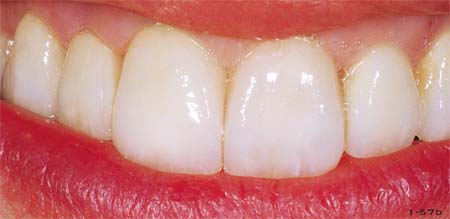

Abb. 1-57c und 1-57d Nahaufnahme des Lächelns vor und nach der Behandlung.

Abb. 1-57e Nahaufnahme der definitiven Versorgung.